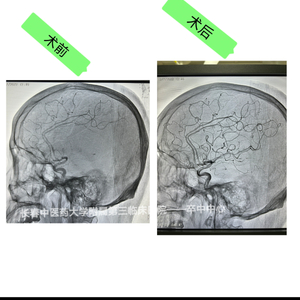

日前,该院卒中中心成功完成首例急性期脑梗死动脉溶栓+脑动脉腔内取栓手术,这也标志该院缺血性脑血管病介入治疗水平迈上新台阶。

随后,脑卒中团队决定急诊动脉取栓应是最佳治疗方案,全体相关人员立即行动,导管室准备、患者术前准备、家属沟通、麻醉评估等工作有条不紊展开,患者在短时间内被推入导管室,在吉林大学中日联谊医院神经外一科于伟东教授和该院多学科共同协作下手术顺利进行。造影证实左侧大脑中动脉起始处完全闭塞,该部位完全闭塞患者往往遗留严重后遗症、甚至死亡,医务部舒遵华主任全程巡视,排除隐患,严保医疗质量安全关,促进团队协作发展。该院介入团队医护人员积极、密切配合,手术护士身穿铅衣在导管室内辅助手术,麻醉医生及时给予镇痛麻醉,于伟东教授、郑军主任、贾世民医生严密配合无缝对接,术中克服各种困难,手术终于顺利完成。

术后当日患者转入ICU观察治疗,次日患者一般状态平稳,精神清醒,脱离危险。转入脑病康复中心进行后续康复治疗。目前,患者运动功能和语言功能已恢复。